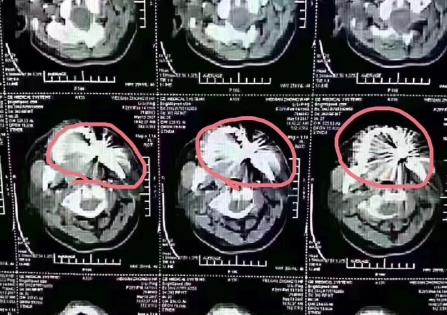

1、內(nei) 冠是普通金屬的烤瓷牙,比如鈷鉻合金,對核磁共振的影響較大,會(hui) 在核磁共振檢查後形成幹擾的偽(wei) 影,而且麵積比較大。因此。一般在核磁共振檢查時需要提前告知工作人員。如果是比較介意對於(yu) 以後檢查有影響的話,不建議選擇這種材料。